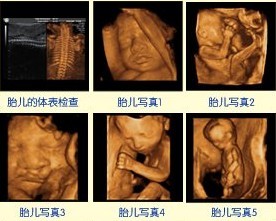

3、四维彩超。四维彩超就是四维成像技术(4D),能直观、立体显示人体器官的三维结构及动态、实时地观察立体结构。四维彩超不再是仅仅感觉宝宝的呼吸和运动,而是可以亲眼目睹他们的一举一动和乖巧的秀容。

美国GE730四维彩超

更为重要的是,四维彩超能够多方位、多角度地观察宫内胎儿的生长发育情况,为早期诊断胎儿先天性体表畸形和先天性心脏疾病提供有效的科学依据。早期发现残疾儿,使医师、孕妇及其家人更的了解胎儿情况,降低残疾儿出生率。